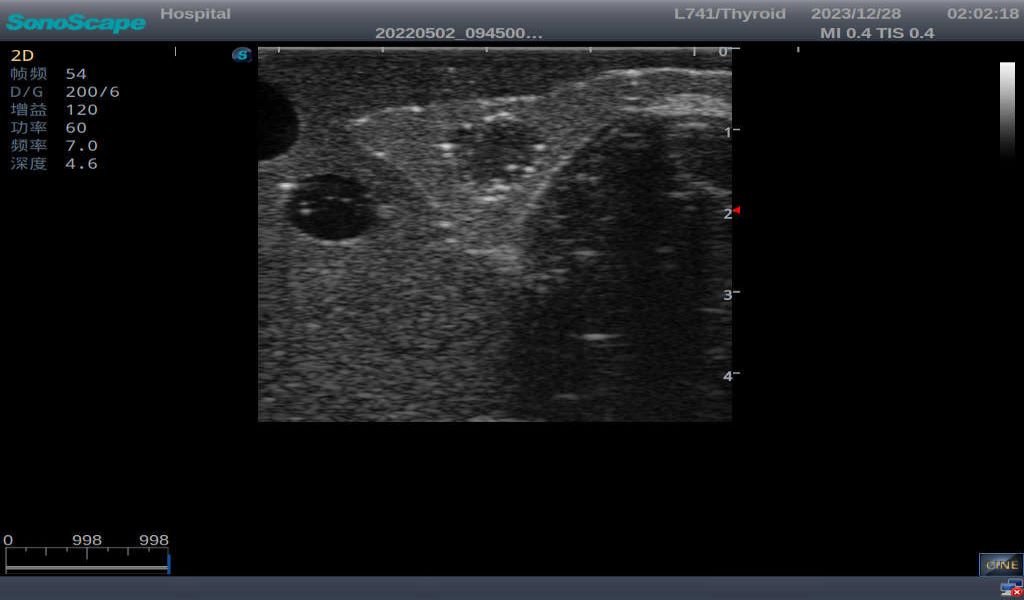

Thyroid Ultrasound Training Model

This product has true-to-life male torso including head, neck, shoulder and upper chest. It serves as an excellent teaching tool for identification of various types of normal thyroid, thyroid adenoma, thyroid cancer, nodular goiter, thyroid cyst and training on proper thyroid scanning techniques.

2)       Ultrasonically realistic materials at neck & various types of real ultrasonic machines in clinical available, developing realistic imaging like common carotid artery, internal jugular vein, trachea, thyroid cartilage, cricoid cartilage, lobes of thyroid gland and isthmus

3)       It comes with four (4) thyroid modules and can show five (5) ultrasonic images: normal thyroid, thyroid adenoma, thyroid cancer, nodular goiter, thyroid cyst

Nodular goiter with irregular border and varying sizes of low echo, isoechoic, or high echo nodules

Thyroid cyst, which fluid area, dark and echo-free area can be seen